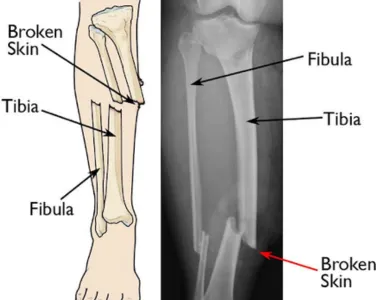

Open Fractures

Specialized care for fractures where bone is exposed, reducing the risk of infection and promoting healing.